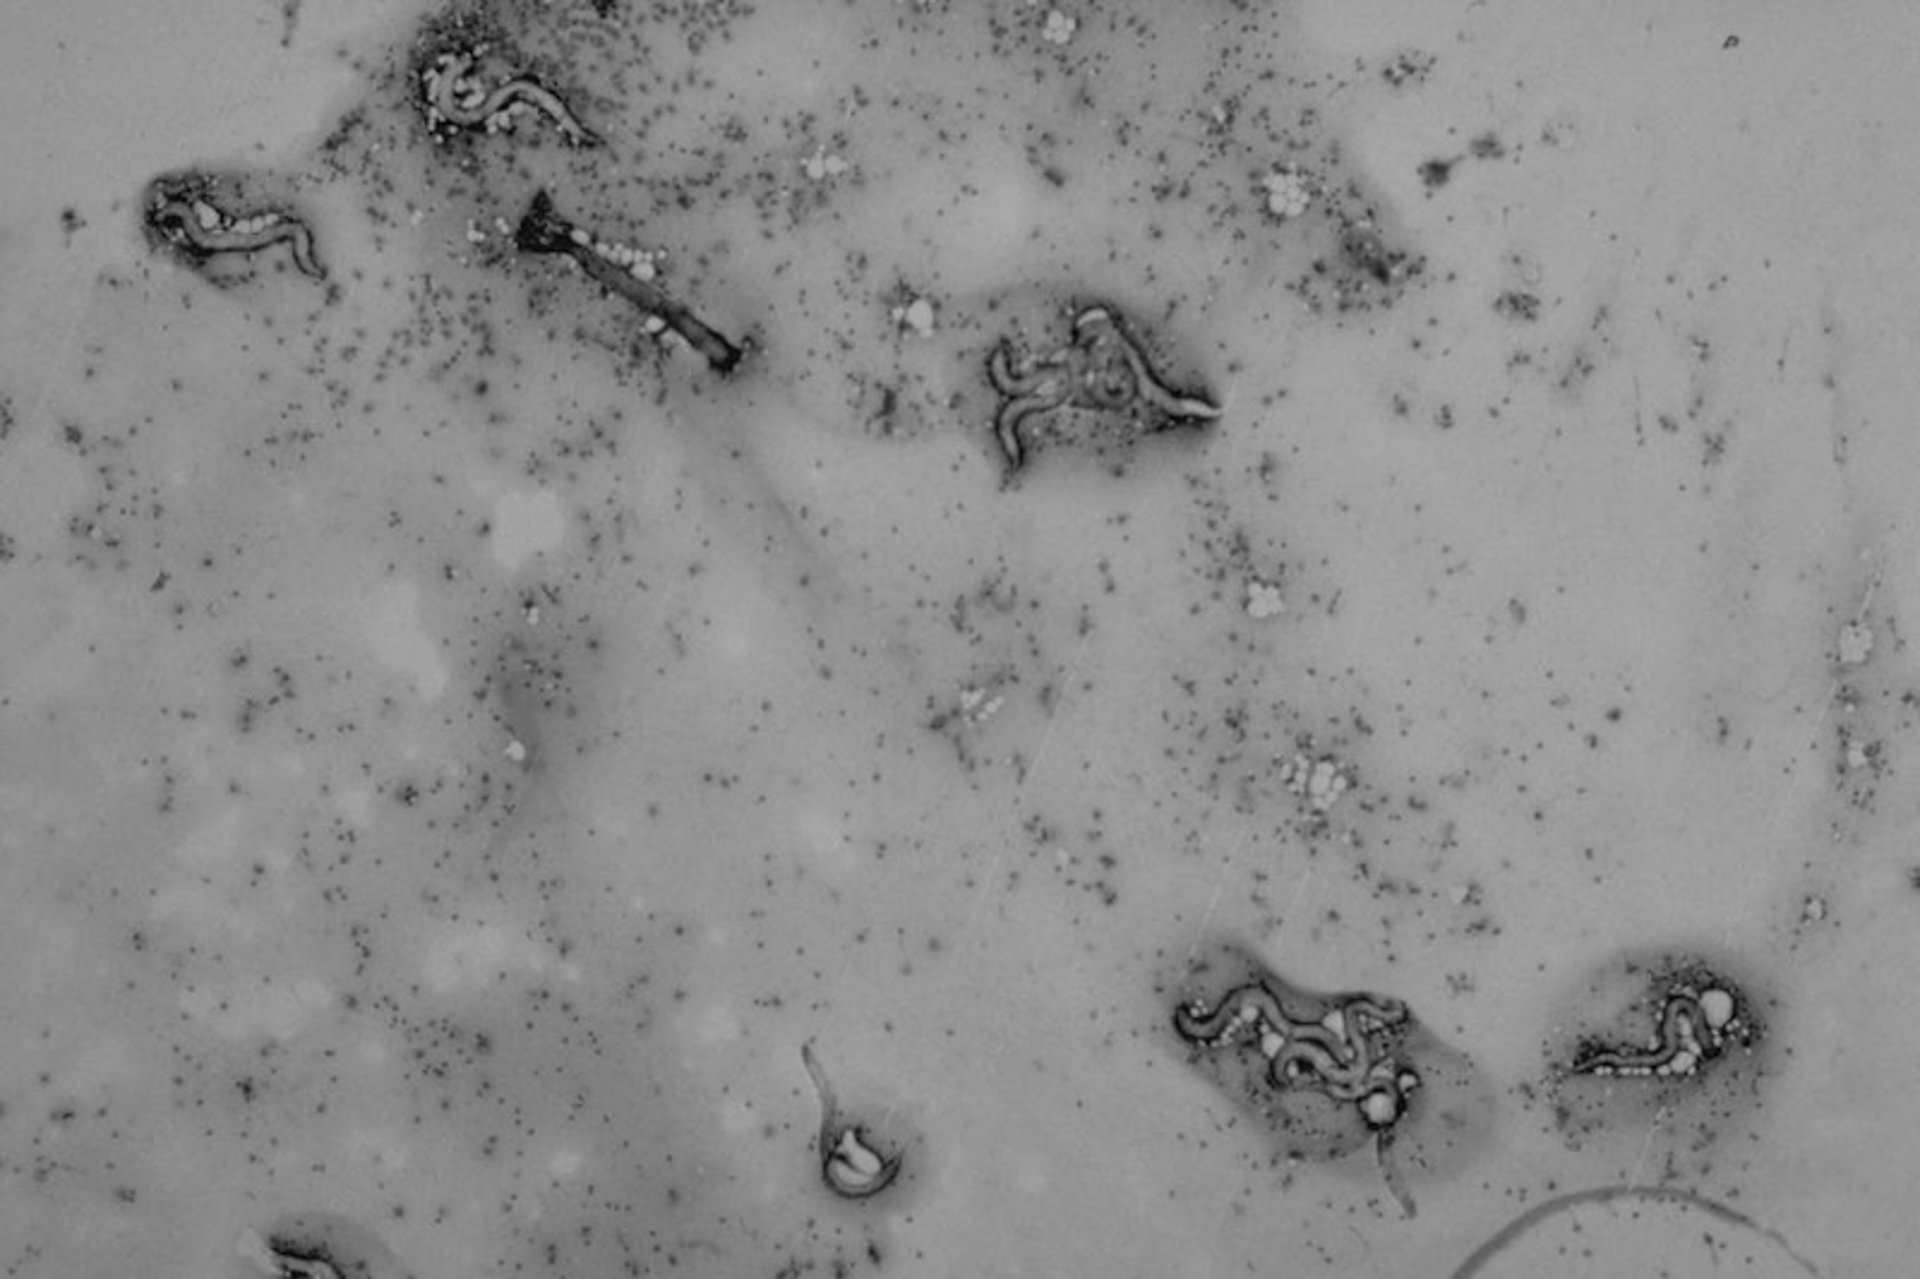

Rhabdias larvae in lung lavage, snake

Rhabdias larvae found in a lung lavage sample. Rhabdias is primarily a parasite of the respiratory system and readily responds to benzimidazoles.

Courtesy of Dr. Stephen Divers.